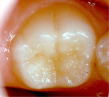

シーラント前 シーラントをした状態